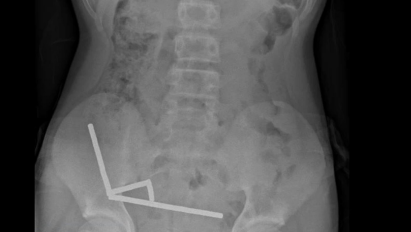

Raio-x abdominal do menino que engoliu entre 80 e 100 ímãs de alta potência • New Zealand Medical Journal

Exames revelaram que os ímãs haviam se agrupado em quatro correntes na parte inferior direita do abdômen, unindo diferentes seções do intestino com sua força magnética, segundo o relatório, que observou que algumas imagens foram distorcidas pelos ímãs. Os médicos então procederam com uma cirurgia exploratória.